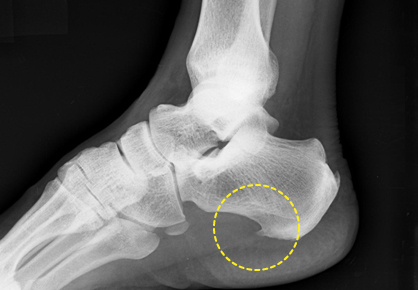

구조적으로 발바닥의 아치가 정상보다 낮아 흔히 평발로 불리는 편평족이나, 아치가 정상보다 높은 요족(cavus) 변형이 있는 경우 족저근막염이 발생할 가능성이 높다. 또한 다리 길이의 차이, 발의 과도한 회내(발뒤꿈치의 바깥쪽 회전과 발목의 안쪽 회전의 복합 운동) 변형, 하퇴부 근육의 구축 또는 약화 등이 있는 경우에도 족저근막염을 유발할 수 있다. 족저근막의 발뒤꿈치뼈 부착 부위에 뼈조각이 튀어나온 사람들 중 일부에서 족저근막염이 발생하기도 한다. 그러나 이와 같은 해부학적 이상이 원인이 되는 경우보다는 발의 무리한 사용이 원인이 되어 발생하는 빈도가 훨씬 높다. 즉 평소 운동을 하지 않던 사람이 갑자기 많은 양의 운동을 하거나, 장거리의 마라톤 또는 조깅을 한 경우, 바닥이 딱딱한 장소에서 발바닥에 충격을 줄 수 있는 운동(배구, 에어로빅 등)을 한 경우, 과체중, 장시간 서 있기, 너무 딱딱하거나 쿠션이 없는 구두의 사용, 하이힐의 착용 등 족저근막에 비정상적인 부하가 가해지는 조건에서 염증이 발생하는 경우가 흔하다. 그 밖에 당뇨, 관절염 환자에서 동반되는 경우가 있다.

족저근막염 X선 영상: 발뒤꿈치뼈에 뼈조각이 자라남